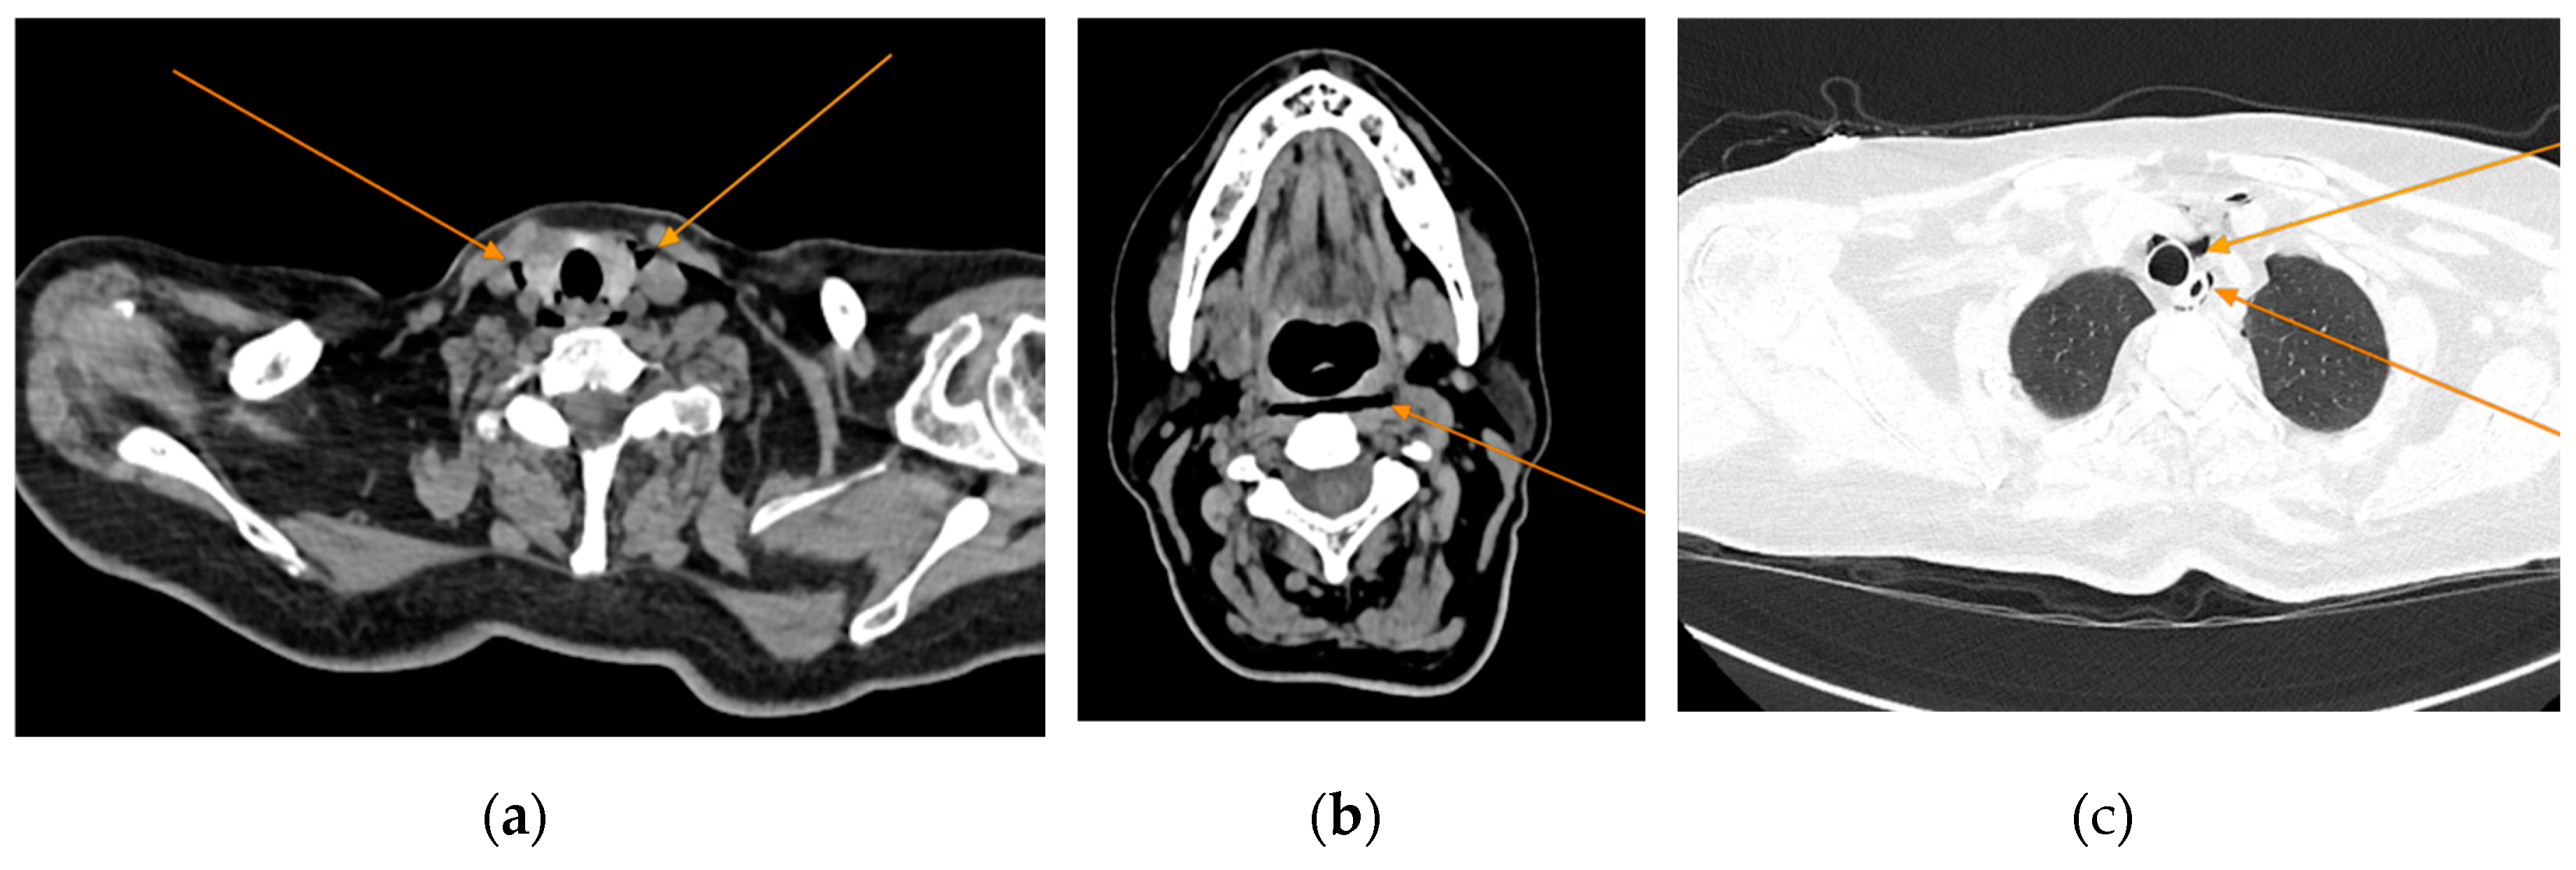

The chest CT scan performed in the emergency department (Figure 1) revealed the presence of pneumomediastinum. CT scans of the abdomen and pelvis were also performed, giving the high lipase and epigastric pain, revealing findings consistent with acute pancreatitis (with peripancreatic fluid collection, consistent with moderate acute pancreatitis per the modified CT severity index), as well as a solitary biliary stone measuring approximately 20 mm in diameter, without intra or extrahepatic biliary ducts enlargement (Figure 2).

Figure 1. Initial chest CT, arrows indicate pneumomediastinum (arrows): (a) axial view; (b) coronal view.

Given the patient’s history of vomiting, and consulting with the thoracic surgeon, a second CT scan with oral contrast was performed approximately 3 hours later, after initial stabilization of the patient, to rule out an oesophageal rupture. The subsequent imaging revealed the progression of the pneumomediastinum, with increased extension into the cervical region, including the peritracheoesophageal, perithyroidal, and retropharyngeal spaces (Figure 3), without evidence of oesophageal rupture (Figure 4). Oxygenotherapy and empiric antibiotherapy were initiated in the ED as initial treatments of this condition.

Figure 3. Repeated chest CT showcasing extension of the pneumomediastinum (arrows), axial views.